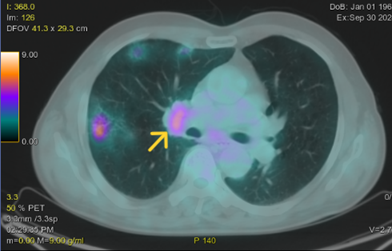

- PET/CT (30/09/2024): Hình ảnh khối mờ ở trung tâm thùy trên phổi phải xâm lấn trung thất, kích thước 70x54mm, tăng chuyển hóa FDG (SUVmax 38.6); Vài đám mờ kính thùy trên phổi phải kích thước 25x22mm, tăng chuyển hóa FDG (SUVmax 8.78); Vài hạch trước khí quản, trước carina, dưới quai động mạch chủ, hạch lớn nhất có đường kính 10mm, tăng chuyển hóa FDG (SUVmax 6.47); Vài hạch rốn phổi phải, hạch lớn nhất có đường kính 11mm, tăng chuyển hóa FDG (SUVmax 5.2); Vài hạch hố nách hai bên đường kính <10mm không tăng chuyển hóa FDG.

Hình 5. Hình ảnh khối mờ trung tâm thùy trên phổi phải xâm lấn trung thất (mũi tên xanh) kích thước 70x54mm, tăng chuyển hóa FDG (SUVmax 38.6); Vài đám mờ kính thùy trên phổi phải (mũi tên vàng) kích thước 25x22mm, tăng chuyển hóa FDG (SUVmax 8.78).

Hình 6. Vài hạch trung thất(mũi tên vàng) hạch lớn nhất có đường kính 11mm, tăng chuyển hóa FDG (SUVmax 5.2).